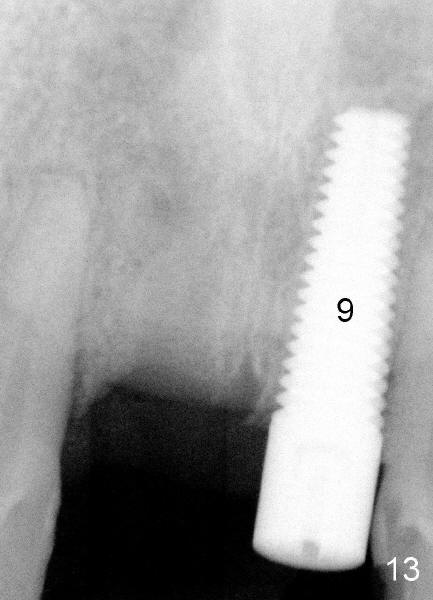

Tooth #8 has an expanding radiolucency (Fig.9 * as compared to Fig.10).  Antibiotic is not going to fix this. Apico surgery will destroy the nice buccal bone (Fig.9 >). I have seen this before, The best choice is to remove the implant with a little curettage at the apex area only. Put a hemostatic gauze, absolutely no bone graft needed. Let it heal for 4 to 6 month. Then implant again.

X-ray in Fig.13 is taken two months after implant removal and immediately before 2nd implant placement.  Round tapered osteotomes (2 and 3 mm) are inserted into the socket.  Then a 4.5x20 mm tapered tap (Fig.14: T) is driven into the socket first by a slow handpiece and second by drill/tap extender (without wrench).  Finally a 5x20 tapered implant is torqued into the recipient socket with some degree of resistance (Fig.15: I).